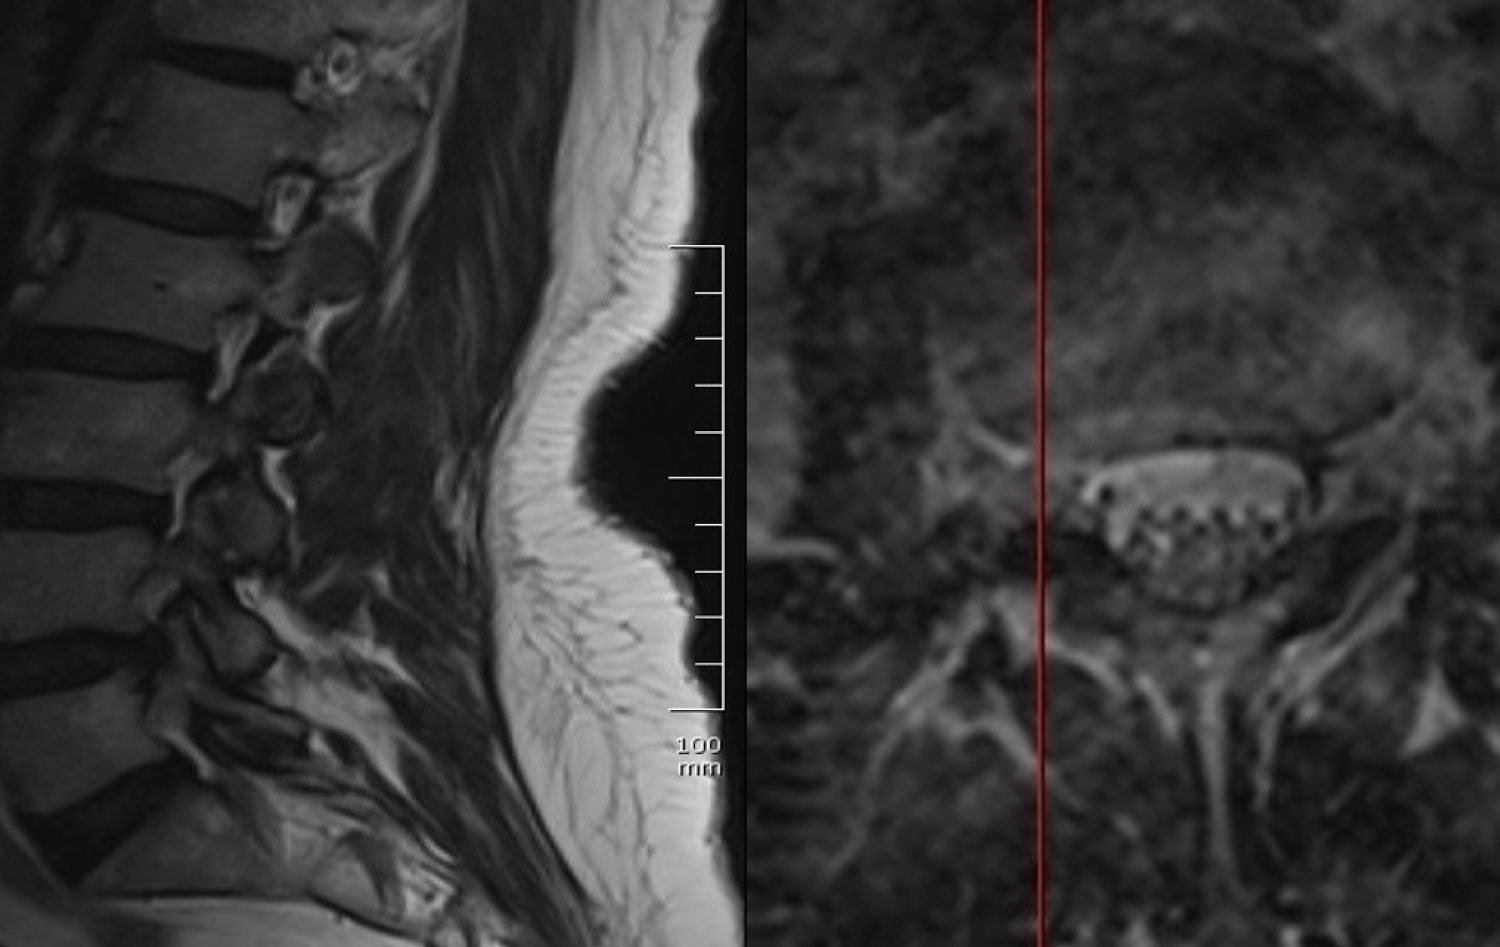

Magnetic resonance myelogram showed no cerebrospinal fluid flow obstruction (Figure 1). Careful evaluation of T1 weighted images showed a hypointense contrast-enhancing mass in the paravertebral muscle originating from the right lumbar (L) 3-4 facet joint (Figure 2). T2 weighted images showed a hyperintense mass in the same region (Figure 3).

Figure 3: T2-weighted sagittal and axial magnetic resonance images. View Figure 3

Radiologically although neurofibromas and schwannomas can look identical, schwannomas are frequently associated with hemorrhage, intrinsic vascular changes (thrombosis, sinusoidal dilatation), cyst formation and fatty degeneration. These findings are rare in neurofibromas. Signal characteristics at T1 weighted images 75% are isointense, 25% are hypointense; T2 weighted images more than 95% are hyperintense, often with mixed-signal; T1 weighted contrast-enhanced images virtually 100% enhances. Due to the structure of the cases that cannot be classified precisely and their similarity to surrounding tissues, magnetic resonance images should be examined carefully. In the present case, although the patient applied to other clinics for a long time, she was undiagnosed due to lack of imaging compatible with the herniated disc clinic. In our case, the lesion was noticed in the axial images with careful observation. We have found magnetic resonance imaging findings sufficient to explain complaints, as it is compatible with the examination. Therefore, no further investigation was requested.